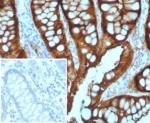

Villin Antibody. Immunohistochemistry analysis of Villin-1 (VIL1) in FFPE human colon adenocarcinoma using Villin Antibody / Microvillus Organization Protein Antibody with recombinant rabbit monoclonal clone VIL1/7378R. Strong HRP-DAB brown staining is observed along the apical membrane of tumor epithelial cells, outlining glandular luminal borders with a dense, continuous pattern consistent with organized microvillus structures. The prominent apical staining highlights actin bundle-rich regions within microvilli and supports Villin function as a microvillus organization protein regulating filament bundling, severing, and capping in epithelial cells.

Villin Antibody. Immunohistochemistry analysis of Villin-1 (VIL1) in FFPE human colon adenocarcinoma using Villin Antibody / Microvillus Organization Protein Antibody with recombinant rabbit monoclonal clone VIL1/7378R. Strong HRP-DAB brown staining is observed along the apical membrane of tumor epithelial cells, sharply outlining glandular luminal borders with a dense, continuous pattern consistent with organized microvillus structures and actin bundle architecture. The pronounced apical localization highlights microvilli-rich regions where Villin regulates filament bundling, severing, and capping. Inset shows negative control tissue with PBS in place of primary antibody, confirming specificity of staining.